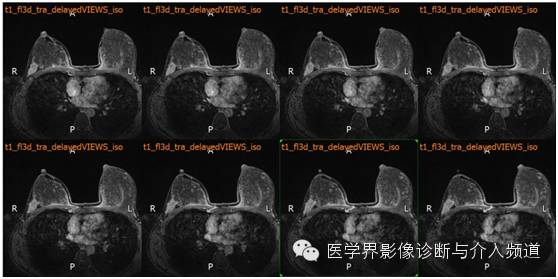

MR平扫及增强示:双乳表面皮肤光整,乳头无凹陷,皮下层次清晰,双乳腺体较丰富,右乳外上象限近胸壁处可见不规则样团状等T1异常信号,FS-T2WI呈高信号,DWI(b=800)示病灶呈略高信号,ADC图呈略低信号,边界不清,并沿导管浸润,范围约4.8×2.5×6.6 cm,双乳内见多发片状、结节样等T1略长T2异常信号。注入GD-DTPA后,上述病灶强化呈”平台”型。右侧胸骨后及腋窝见多发淋巴结影,较大者位于右侧腋窝,最大径约0.8 cm。